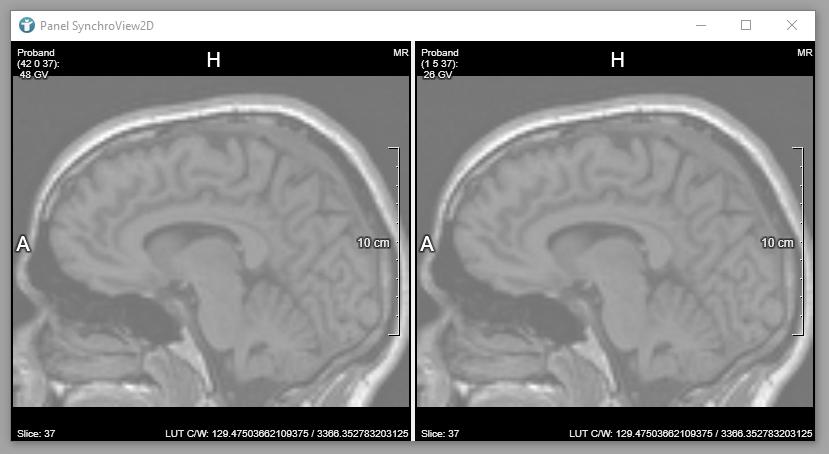

SynchroView2D and change window/level values via right mouse button

. You can see that the background of your images gets very bright and changes based on the LUT are applied to all voxels of your input image - even on the background. Hovering your mouse over the image(s) shows the current gray value under your cursor in Hounsfield Unit (HU).